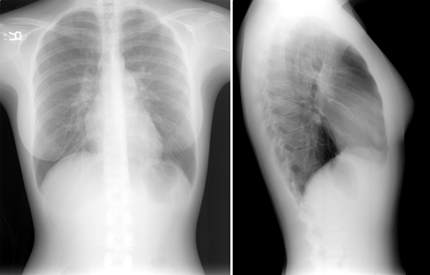

A 32-year-old woman presents for evaluation of a murmur recently

heard on physical examination. She has noted mild reduction in

exercise capacity over the past 6 to 12 months. She has no known

history of cardiovascular disease, although a murmur was reported

early in life. Following a physical exam and chest radiograph, what

is the most likely diagnosis in this patient?